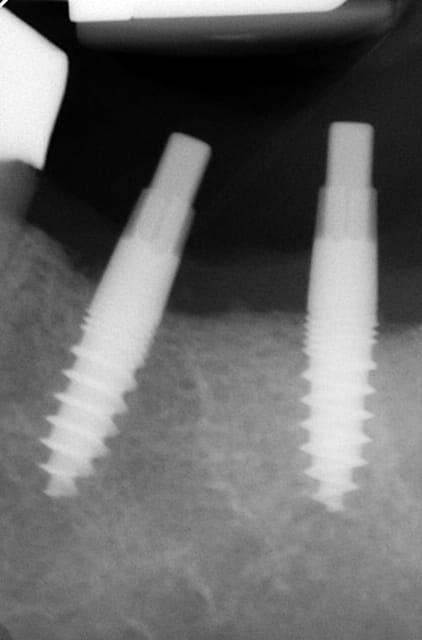

Maintenant concernant la demande de scans : je poste ce cas, une patiente vient me voir avec son scan car elle a consulté d'autres "spécialistes" et on lui refuse la pose d'implant secteur 4 où alors avec greffe préalable..Ca se discute..pas de temps à perdre je sais faire autrement..

Avec la chir trans gingivale technique MIMI ( Oui..un post sur la technique bientôt ..) j'ai pu placer deux 3,5/8mm..aurai je eu le meme résultat avec un lambeau..j'en doute..Les couronnes sont en titane. Recul clinique 2 ans ras. Simple efficace rapide moins onéreux satisfaisant pour le praticien et la patiente..